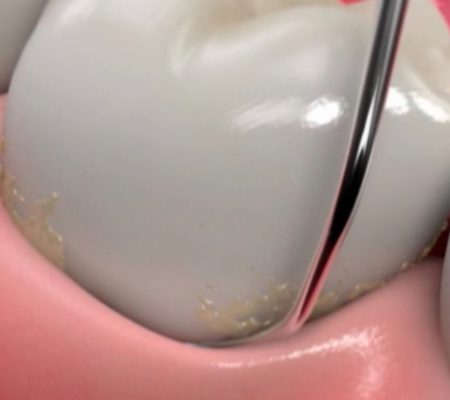

Teeth cleaning removes plaque to prevent cavities and gum disease.

Composite restores decay and enhances tooth color or shape.